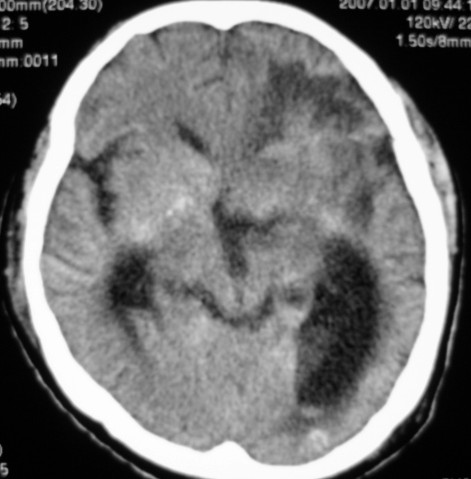

标题: CT9218:男性,50岁,脑出血术后复查,两次片相隔半月,请分 [打印本页]

标题: CT9218:男性,50岁,脑出血术后复查,两次片相隔半月,请分

第一次ct片脑出血术后,出血吸收期。第二次ct 片左颞顶枕部及右颞顶部有脑回样高密度影。考虑珠网膜下腔出血。脑出血术后改变,脑出血恢复期 并脑积水。

第一次ct片脑出血术后,出血吸收期。第二次ct 片左颞顶枕部及右颞顶部有脑回样高密度影。考虑珠网膜下腔出血。脑出血术后改变,脑出血恢复期 并脑积水